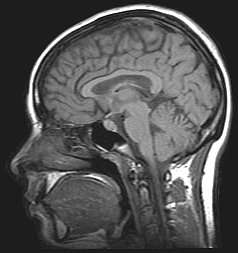

Functional magnetic resonance imaging (fMRI) has intriguing implications for the study of memory in humans, however it can also be used in animal models. fMRI can be used to assess brain functionality in monkeys in the context of a variety of behavioral tasks.[26] Structural MRI can be used to examine the extent and location of brain lesions, so that behavioral abnormalities observed can be directly linked to specific brain structures.[27] High-resolution fMRI can help locate and assess the functionality of large neural networks so that these regions can be further studied using more traditional electrophysiological recording devices.[26]